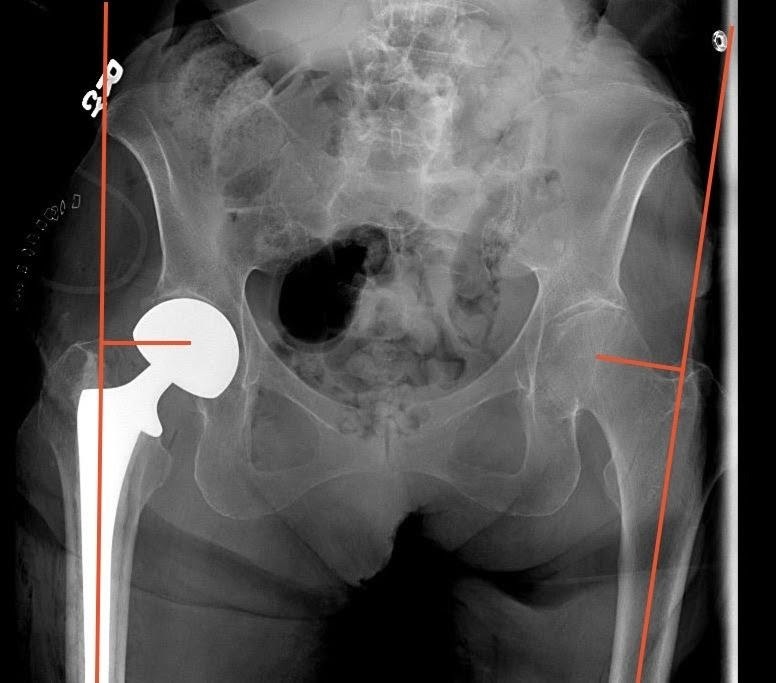

Measurement of FO was also performed using immediate postoperative imaging of an AP pelvis radiograph utilizing the technique described by Asayama et al.15 This technique measures the distance from a vertical line drawn from the center of the femoral head to a line bisecting the femoral shaft. Positive values were given if the operative side had a greater offset than the contralateral side, and negative values were given if the operative side had less offset (Figure 4).